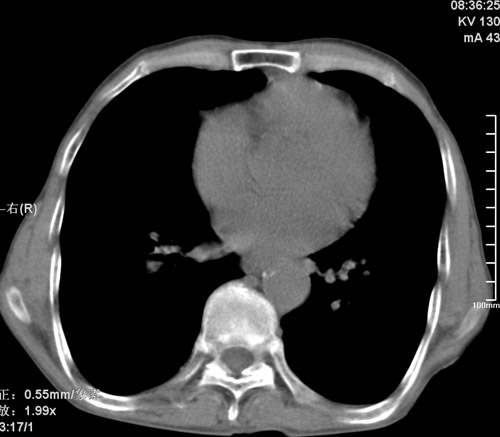

标题: CT17529:男 76 胸背部不适半月 胸透支气管炎 行CT检查 [打印本页]

标题: CT17529:男 76 胸背部不适半月 胸透支气管炎 行CT检查

意见 老年肺 少许炎症 肺大泡 右肺门略大 但支气管通畅  请各位高手指教如何下意见

支持楼主意见,右肺门略大,可能为肺动脉增粗.

慢支肺气肿,肺动脉高压.